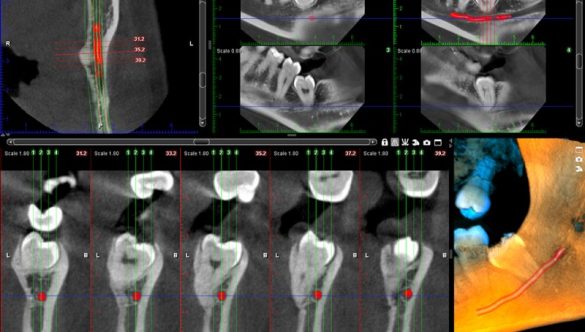

TOMOGRAFIE DENTARĂ ÎN SCOP ENDODONTIC

Tratamente endodontice sigure, cu cea mai performantă tomografie dentară digitală, în cadrul Centrelor de Radiologie …